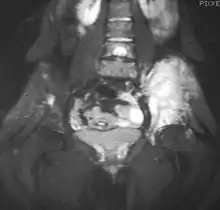

![]() ![]() | |

| Top: Ewing sarcoma of the thigh bone on a child's CT scan Bottom: Extraskeletal Ewing sarcoma of the hard palate | |

It can occur anywhere in the body, but most commonly in the pelvis and the long tubular bones, especially around the growth plates.[1] The diaphyses of the thigh bone are the most common sites, followed by the tibia and the upper arm bone. Around 25% have spread at presentation.[1] In soft tissue, it can affect a wide distribution of the body.[6] Rarely, it can develop in the cervix, vagina and vulva.[10]